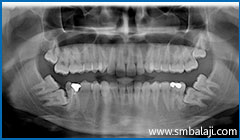

All impacted teeth removed